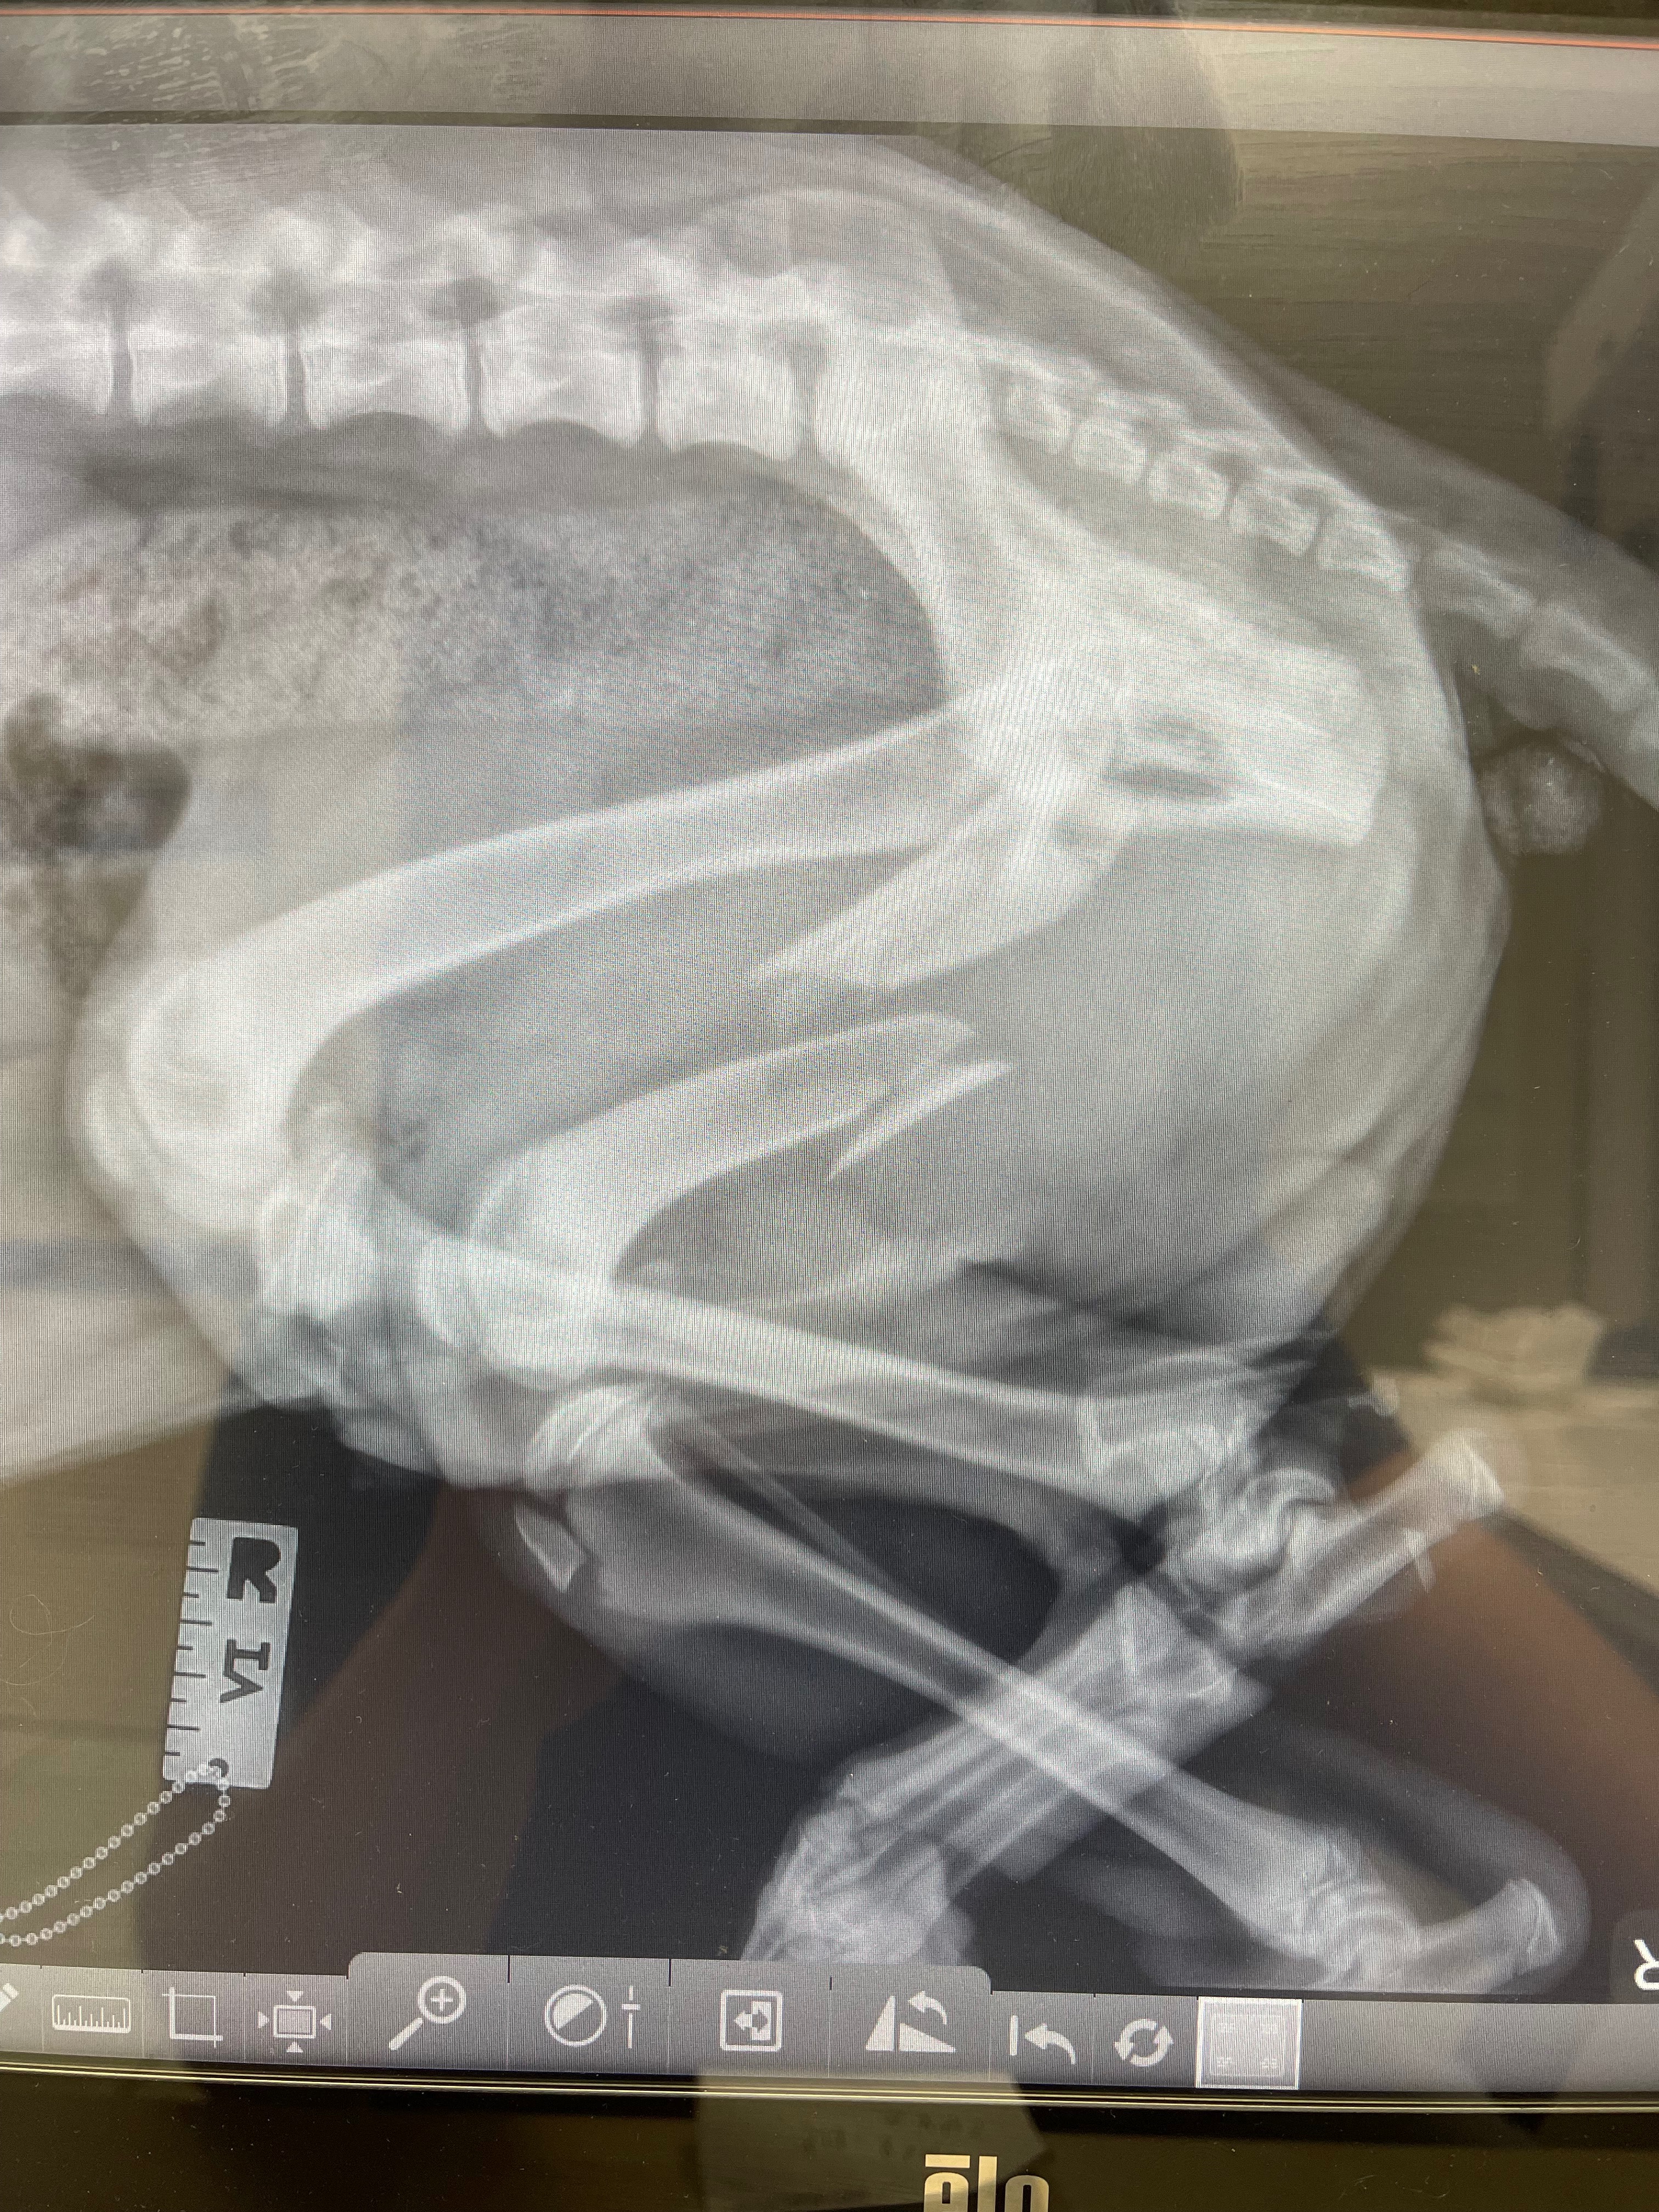

Recently, Koda was hit by a teenage driver on our street. Our neighbor’s young grandson tried to prevent the accident, but the driver hit Koda and kept going. Koda is now at the vet, undergoing testing and pain treatment to prepare for surgery. He has a fractured left shoulder, a completely shattered left femur, a fractured left knee, road burn on his face, a lacerated tongue, and a few broken teeth. It’s heartbreaking to see him in pain, but we are doing everything we can to help him recover. We are so thankful to all of the neighbors who stopped to offer assistance during this difficult time—their kindness and support have meant so much to us.